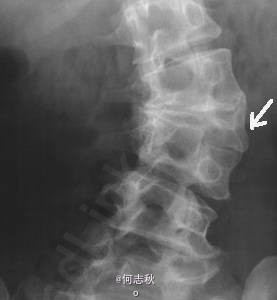

体格检查:患儿智力、生长发育正常,双弓足高。平第2腰椎处皮肤可见1.8cm×2.0cm褐青色斑块,稍隆起皮面,边界不清,颜色不均,其上可见黑色毛发穿出。 辅助检查:脊柱x线片示骶1隐性脊柱裂,余腰骶椎骨质未见异常;血生化示血尿酸单项略高。

诊断:隐性脊柱裂伴局部先天性多毛性皮肤色素异常 处理:患儿局部多毛性皮肤色素异常无需特殊治疗,隐性脊柱裂所致临床症状轻微,不需手术治疗,嘱其加强腰背肌锻炼,出院随访。